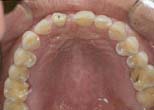

Forced eruption